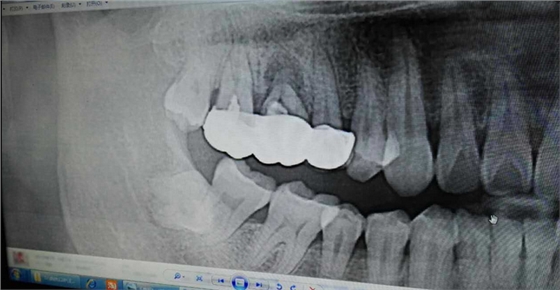

病例:患者男性47歲

右下8骨埋伏并且黏連;從根分叉處通過;有彈性;術(shù)中看到神經(jīng)束

實在找不到;近中牙冠沒去干凈

像這種不切除的牙冠,以后吸收的可能性不是很大,但有排除的可能性,自己自行排出,要是牙根的話吸收的可能性比較大

像這種沒有癥狀的殘留牙體組織不用去除可以吧